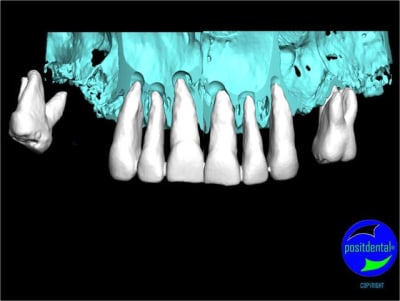

rendu 3D maxillaire sup, pano et photo

3D maxillaire inférieur et photo